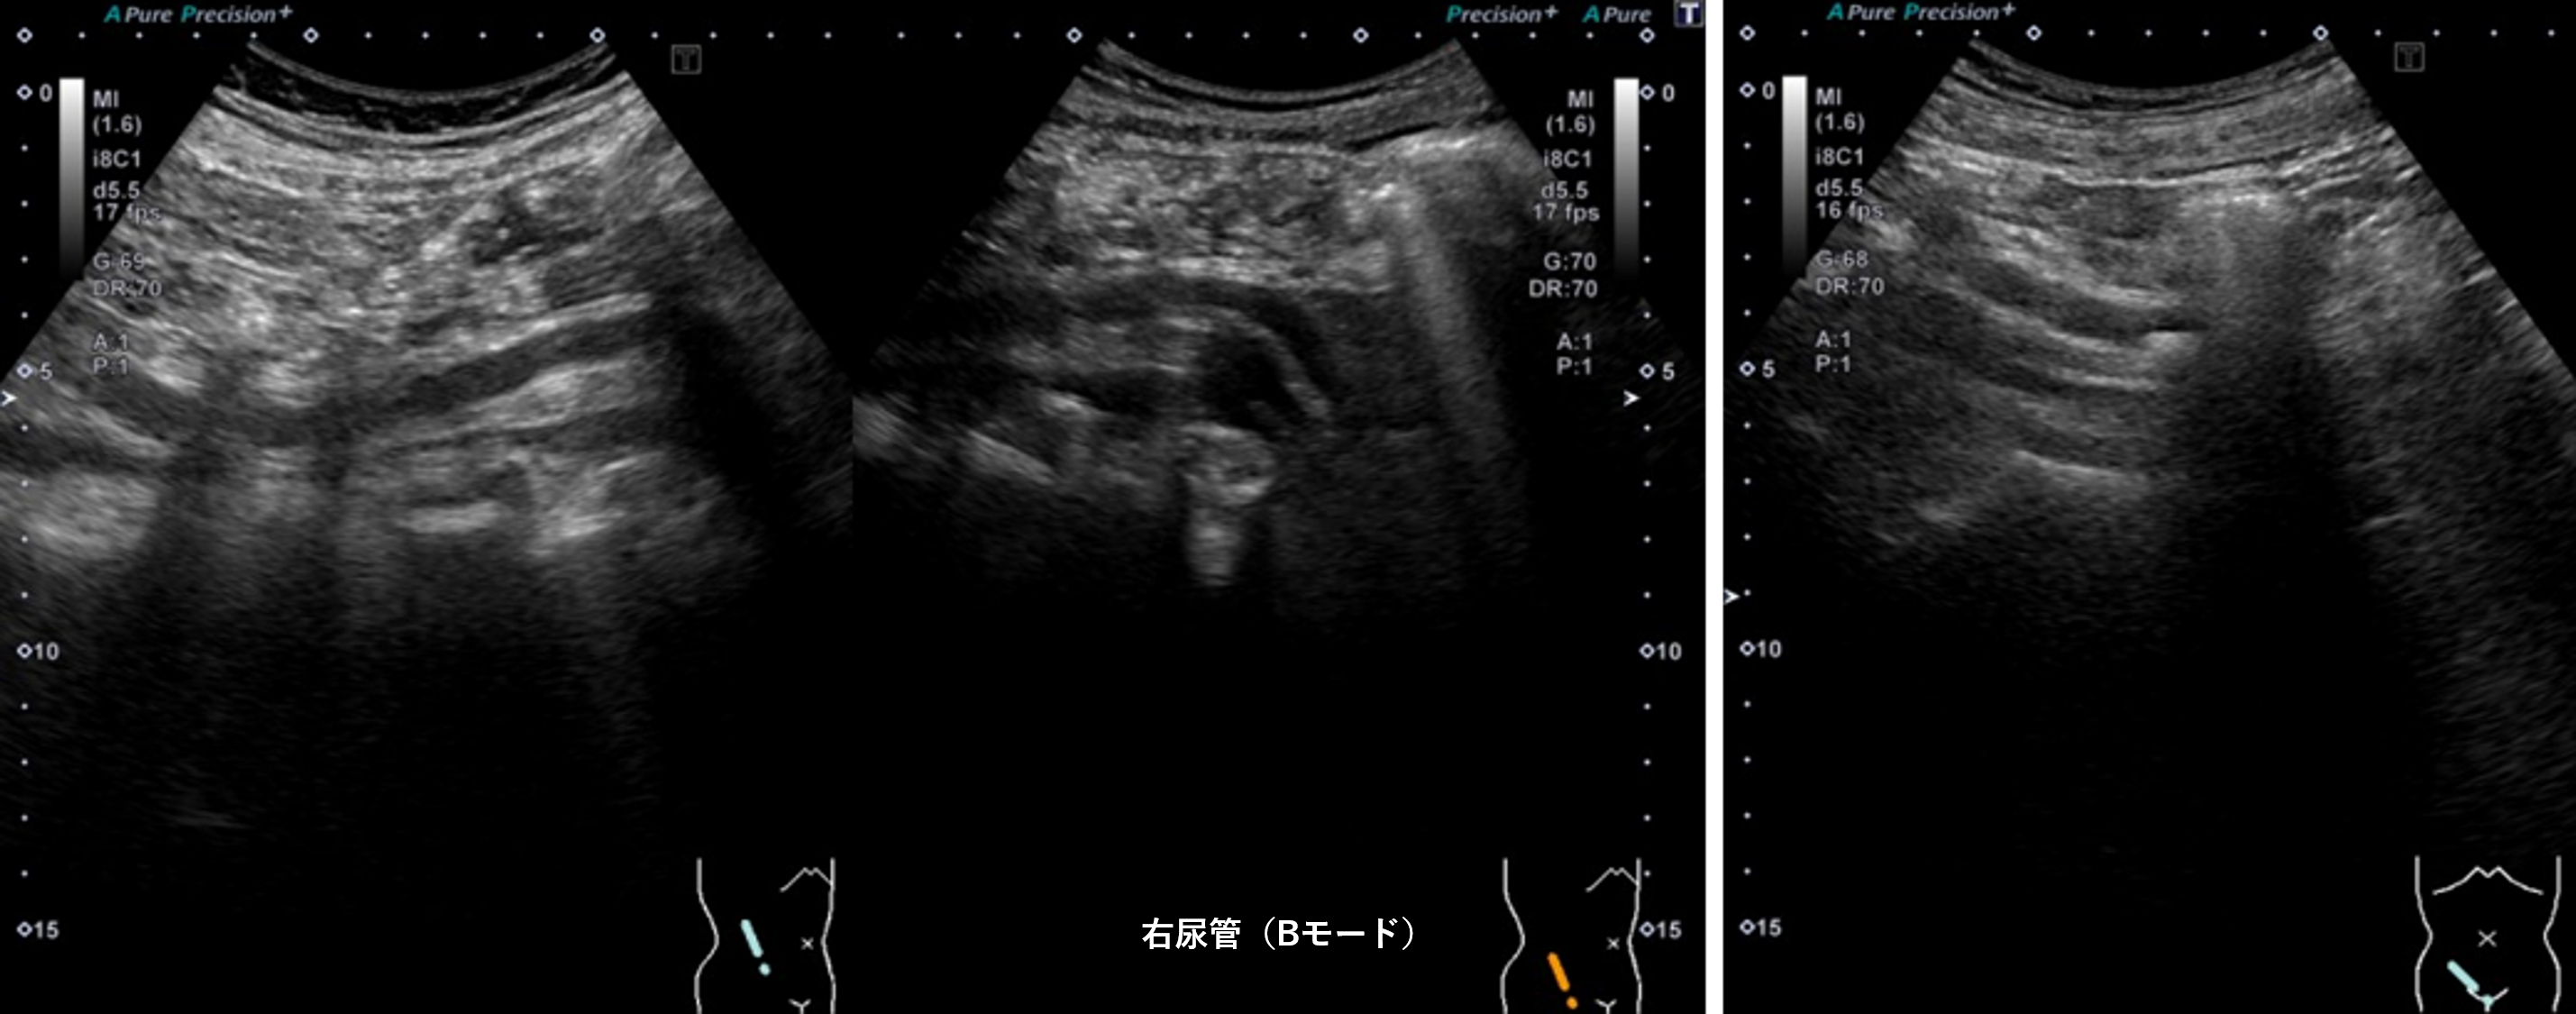

腹部超音波2 動画3 右尿管(No18-19_C)

腹部超音波2 動画3(No18.19_C)

① 右尿管内に充実性腫瘍像を認める

④ 右腎の腎盂拡張および右尿管拡張を認める